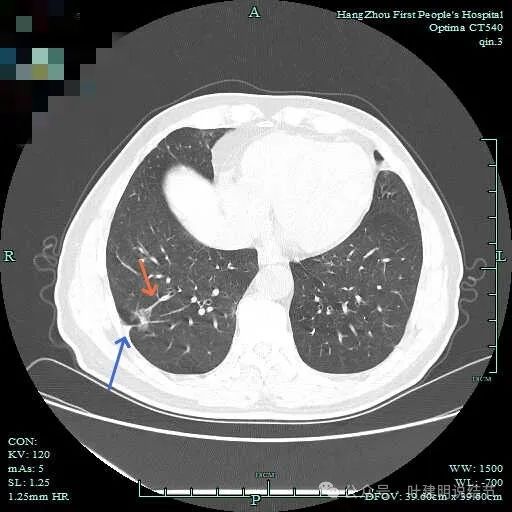

次病灶连续层面观察:

紧贴脊柱处混合密度,趴在脊柱上,这不像结节状。

但有小血管似的,磨玻璃部分界限较清。但此类异常影像在正常人的CT上也挺常见。

密度较高,确实像血管进入。但病灶片状,趴在脊柱上。

此层显得更呈小片状了。

与脊柱间似乎有间隙在,另见微小血管进入这条索状的偏高密度影处。

有细小血管进入,但说不上异常增粗。病灶仍是小片状,条状。

磨玻璃成分密度淡且界欠清,整体就是条索状弯曲的。

上图见细毛刺明显。

病灶实性伴细毛刺,与脊柱间有间隙在。

病仍明显,从上到下,觉得应该是成片的。

表面不平毛刺,实性密度为主。

微小血管有,但无异常增粗。

病灶实性,边缘不光滑。

实性密度,片状,条状。

病灶实性,缺乏膨胀性。

上图呈结节状,表面不平,有少许磨玻璃成分。

结节状,密度高,边缘欠光滑。

与脊柱之间有间隙,表面有细毛刺。

表面不平,似有细支气管截断征。

边缘不平毛糙。

像慢性炎似的。

瘤肺边界欠清。

边缘区淡磨玻璃密度。